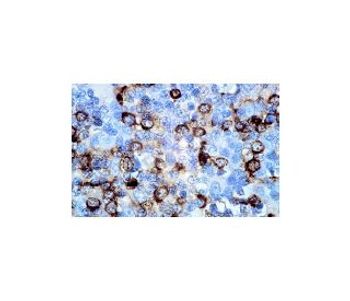

mouse monoclonal IgG2a; CD8 Antibody (UCH-T4) is an IgG2a κ mouse monoclonal CD8 antibody that detects CD8 of human origin by IP, IF, IHC(P) and FCM. CD8 Antibody (UCH-T4) is available as the non-conjugated anti-CD8 antibody form, as well as multiple conjugated forms of anti-CD8 antibody, including agarose, HRP, PE, FITC and multiple Alexa Fluor® conjugates. The T cell receptor (TCR) is a heterodimer composed of either α and β or γ and δ chains. CD3 chains and the CD4 or CD8 co-receptors are also required for efficient signal transduction through the TCR. The TCR is expressed on T helper and T cytotoxic cells that can be distinguished by their expression of CD4 and CD8; T helper cells express CD4 proteins and T cytotoxic cells display CD8. CD8 (also designated Leu 2 or T8), a cell surface glycoprotein, is a two chain complex (αα or αβ) receptor that binds class I MHC molecules presented by the antigen-presenting cell (APC). A primary function of CD8 is to facilitate antigen recognition by the TCR and to strengthen the avidity of the TCR-antigen interactions. An additional role for CD8-expressing T cells may be to maintain low levels of HIV expression.